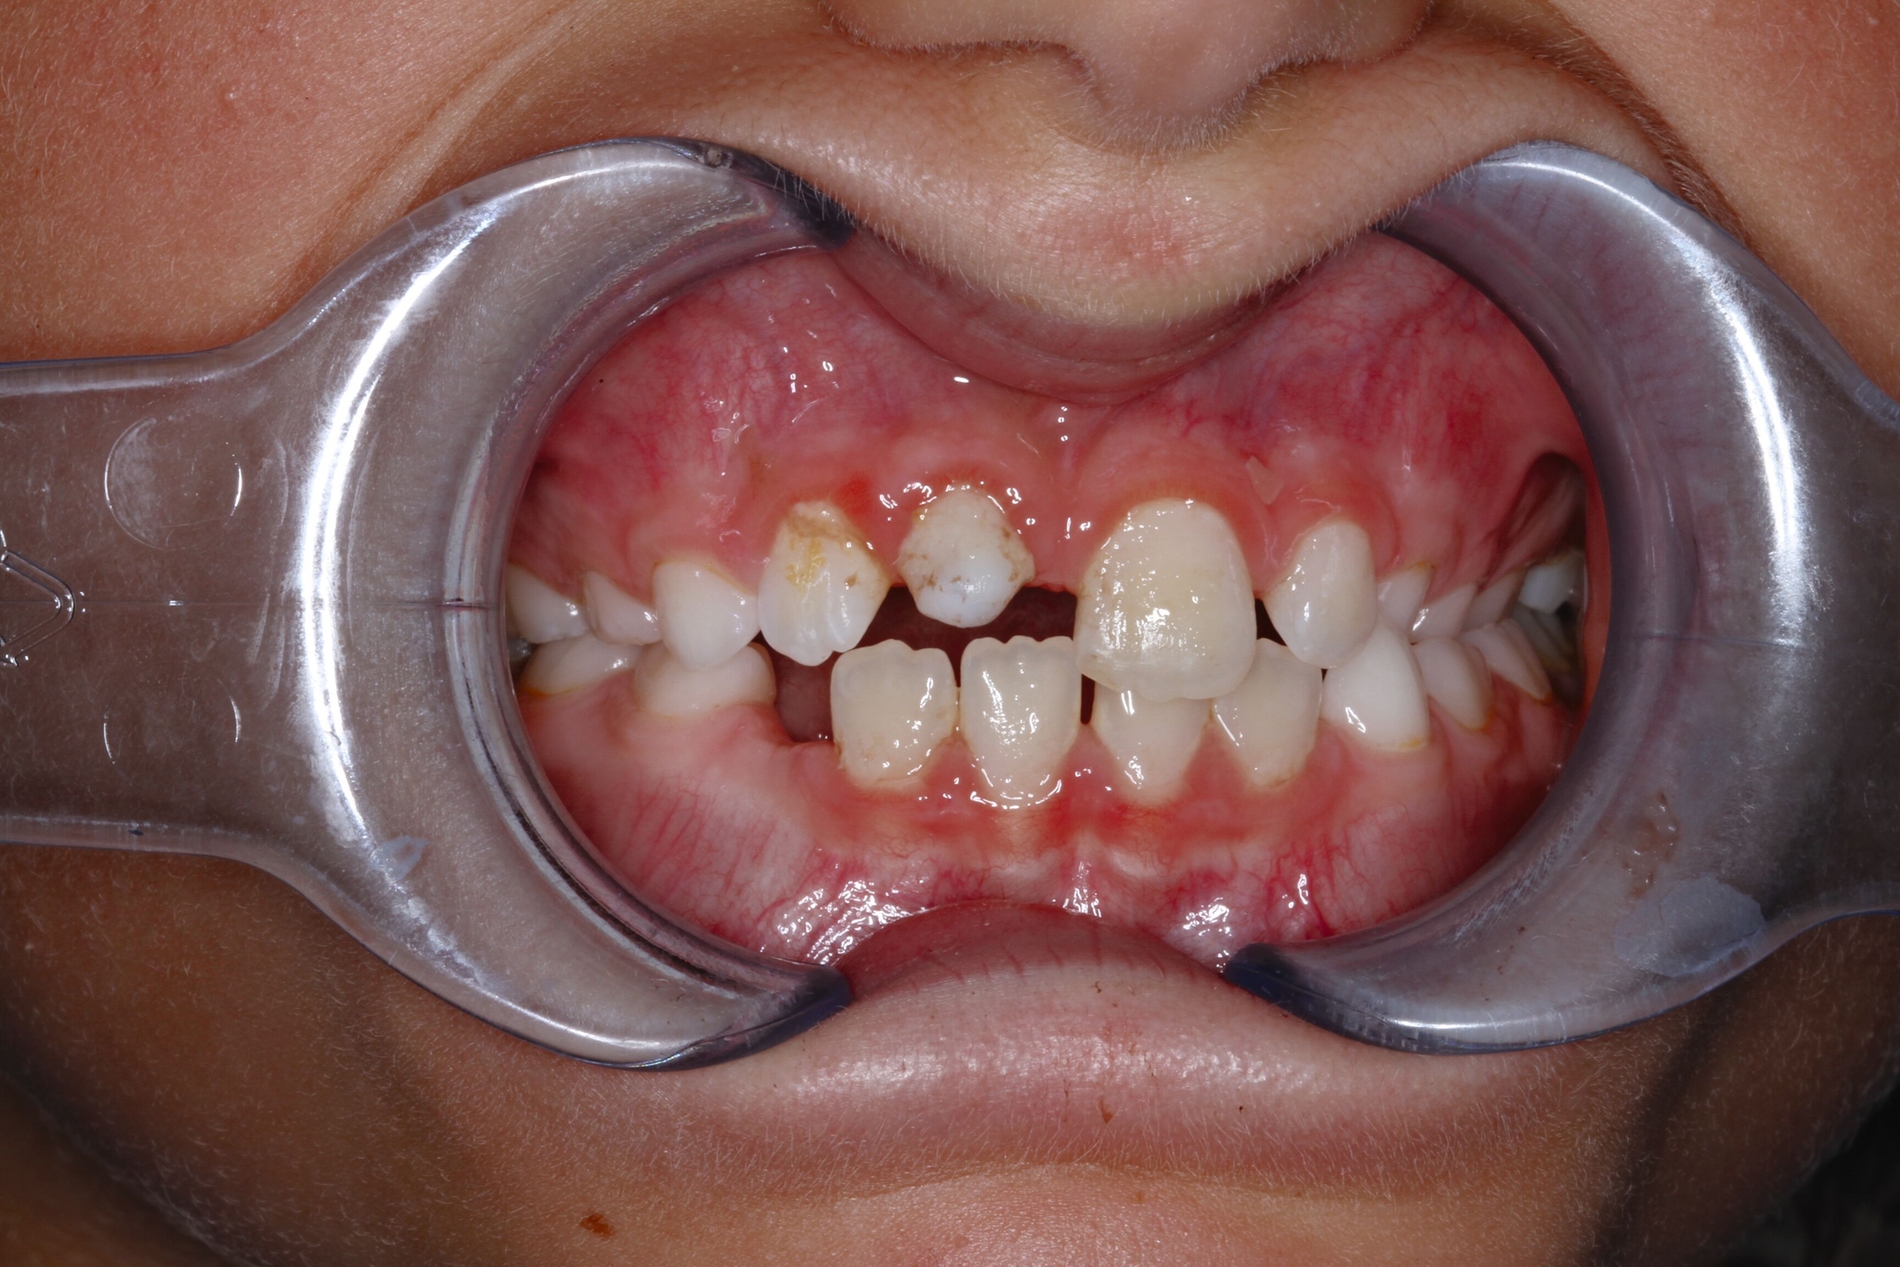

Aufgrund der infausten Prognose des replantierten Zahnes 11 entschieden wir uns für die Milchzahn-Transplantation von 83 nach 11, da dieser die längste Wurzellänge aller vier Milcheckzähne besaß. Im selben Eingriff wurde der replantierte Zahn 11 entfernt und der Milcheckzahn 83 in die Lücke 11 transplantiert. Das Transplantat wurde für drei Wochen mit einer Überknüpfnaht fixiert, die mit Kunststoff (Tetric EvoFlow®, Cavifil, Bleach XL) adhäsiv gesichert wurde (Abbildung 3a). Nach der Entfernung der Naht zeigte sich ein reizlos eingeheiltes Transplantat mit Lockerung I. Grades, negativem Perkussionstest sowie reizlosen gingivalen Verhältnissen bei einer Taschentiefe von 1 mm (Abbildung 3b).

Das Transplantat wurde acht Wochen später schrittweise in adhäsiver Technik mit Komposit aufgebaut (Abbildungen 4a und 4b) und blieb so für weitere 4,2 Jahre – funktionstüchtig – im Mund der Patientin, bis ins Alter von 13,2 Jahren. Die psychosozialen Folgen dieser sofortigen ästhetischen Rehabilitation können gerade bei Mädchen gar nicht hoch genug eingeschätzt werden.